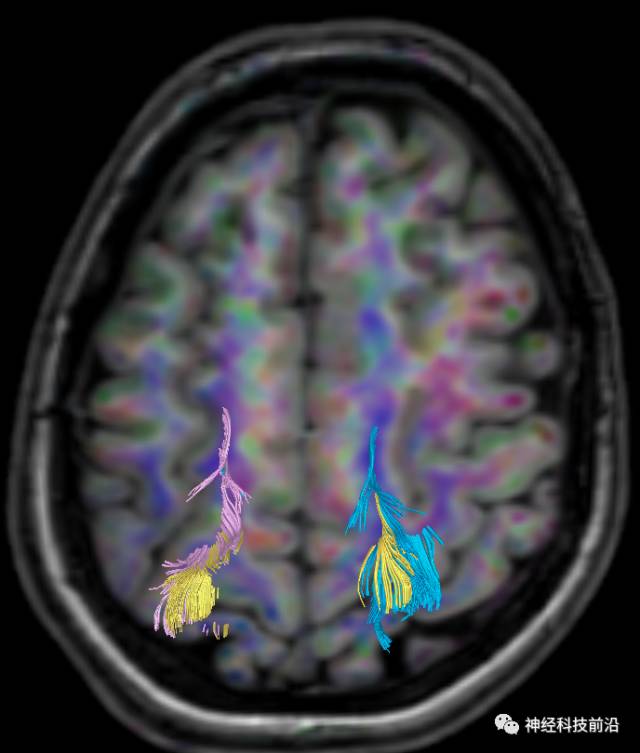

皮质脊髓束与皮质脑桥束的关系毗邻

终上所述:脑干高信号为一近环形纤维束,内囊后肢高信号为皮质脑桥束,皮质脊髓束在中脑位置略靠后。高信号位于中脑前缘,是皮质脑桥束的位置所在,另外有部分桥连纤维。